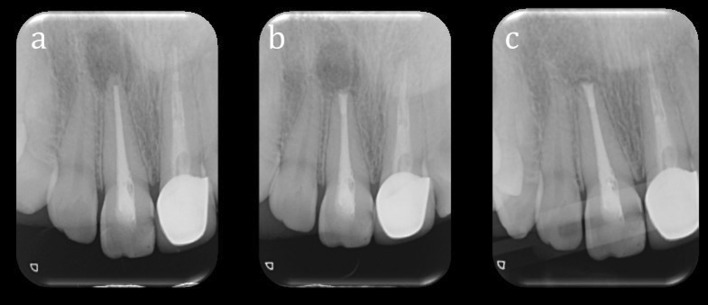

The postoperative radiographs taken at 6 months were evaluated independently by two examiners using the criteria established by Rud et al. [10] (Figs. 2, 3). The two examiners standardized the evaluation criteria before case analyses. Any disagreement regarding the clinical outcome was resolved by discussion until an agreement was reached. The following healing classification was used based on the criteria proposed by Rud et al. [10]:

Fig. 2.

Preoperative (a), immediately postoperative (b) and 6 months postoperative (c) periapical radiographs of a patient included in this study